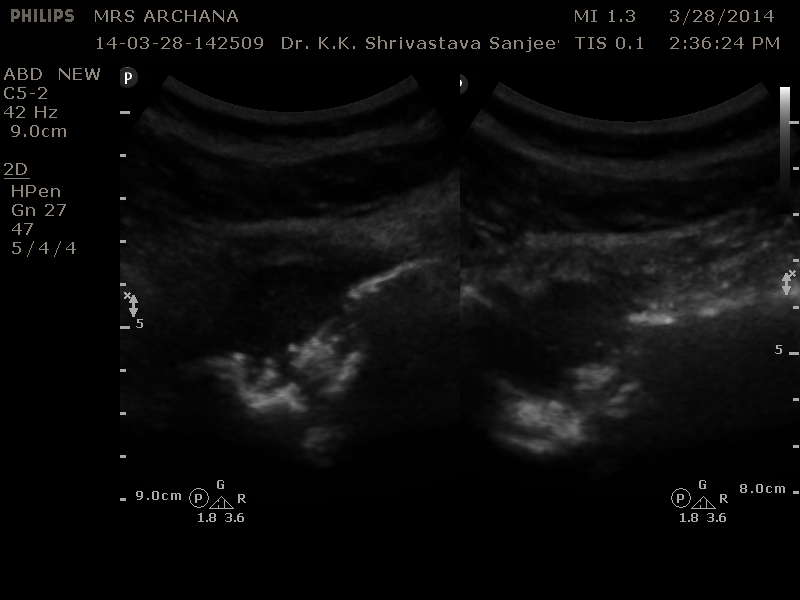

She was carrying a good quality Radiograph of both S.I.Joints AP view Reported Sacroilitis, left side

Also an MRI both S. I. Joints : Reported Sacroilitis Left S.I. Joint .

Left S.I. Joint shows altered configuration with underlying cortical destruction of bony land marks as compared to the right side.

Targeted view of the left S.I. Joint is showing distended capsule with homogenous fluid collection associated with cortical erosion of the sacral and ileum articular surfaces.

Provisional diagnosis of cold abscess secondary to Koch’s Left S.I. Joint was made .